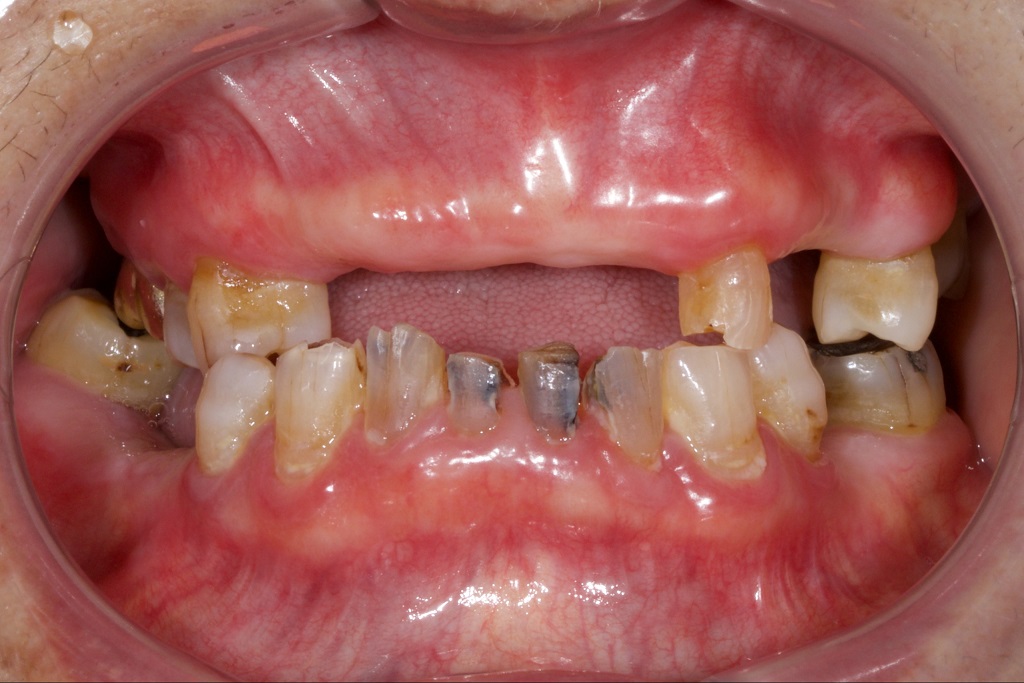

Dry mouth is among the most destructive complications of Sjögren’s. In a healthy mouth, saliva rinses away food particles, balances oral pH, and shields enamel against bacterial acids. In Sjögren’s patients, the absence of saliva keeps the oral environment persistently acidic, accelerating decay and weakening tooth enamel. When compounded by GERD, which introduces stomach acid into the oral cavity, the risk of rapid, severe tooth damage multiplies. Sticky bacterial plaque thrives under these conditions, eroding enamel and creating an ideal environment for cavities to form quickly and aggressively.